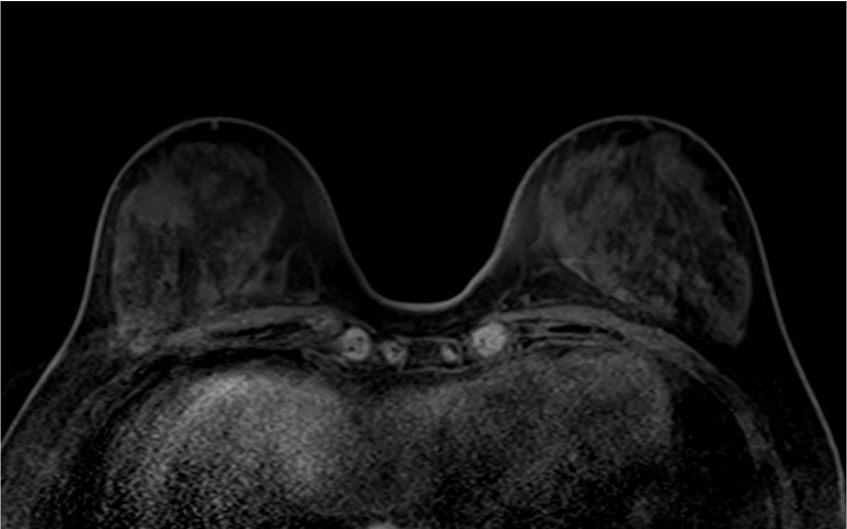

2. T2強調画像 (造影前)

乳癌の病変は、背景乳腺より軽度高信号の腫瘤を示している。明らかな腫瘍内壊死や周囲の浮腫は認めない

3. T1強調画像 (造影前)

乳癌の病変は、辺縁不整な腫瘤(Mass)を示している。

造影前